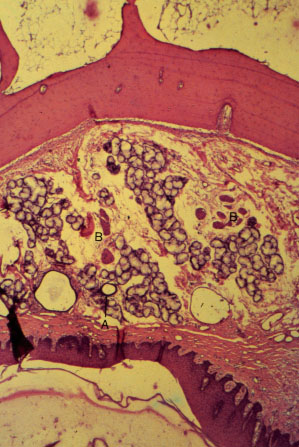

K-slide 38: Still higher magnification of slide 36

A. Anterior palatine artery

B. Branches of anterior palatine nerve